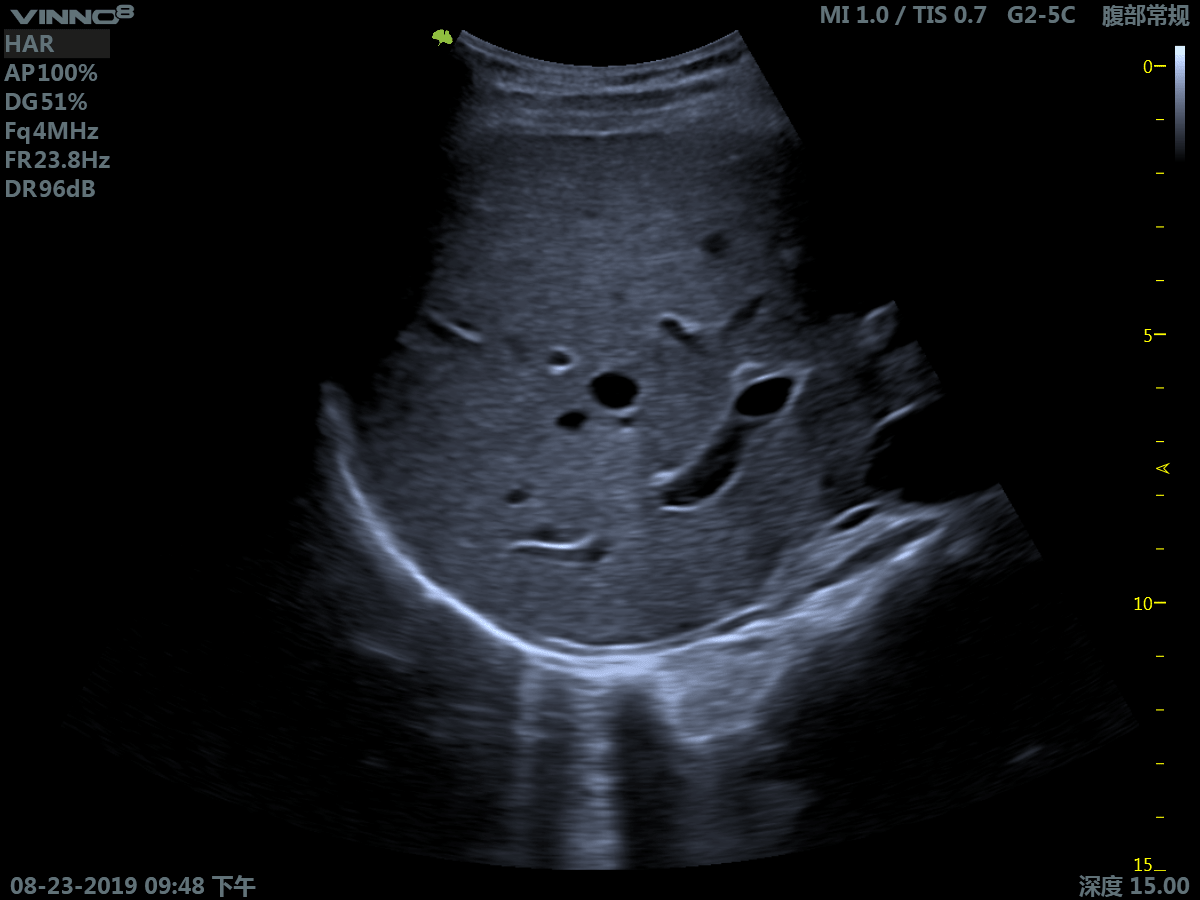

Клиническое применение:

- брюшная полость

- гинекология

- урологическое (включая простату)

1. B-режим. Позволяет получить двухмерное плоскостное изображение на некоторой глубине расположенных рядом структур и их движение во времени.

3. Режим тканевой гармоники - технология выделения гармонической составляющей колебаний внутренних органов, вызванных прохождением сквозь тело базового ультразвукового импульса.